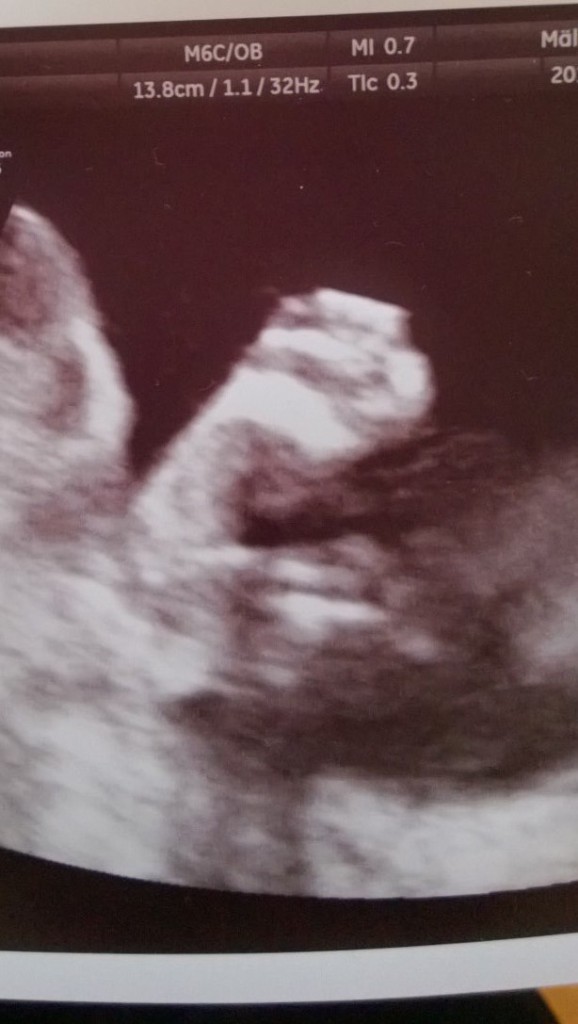

min dotters fot på första ultraljudsbilden=) jag längta så efter henne! jag fick 4 ultraljud tack vare min problematiska graviditet. så jag har många bilder=D